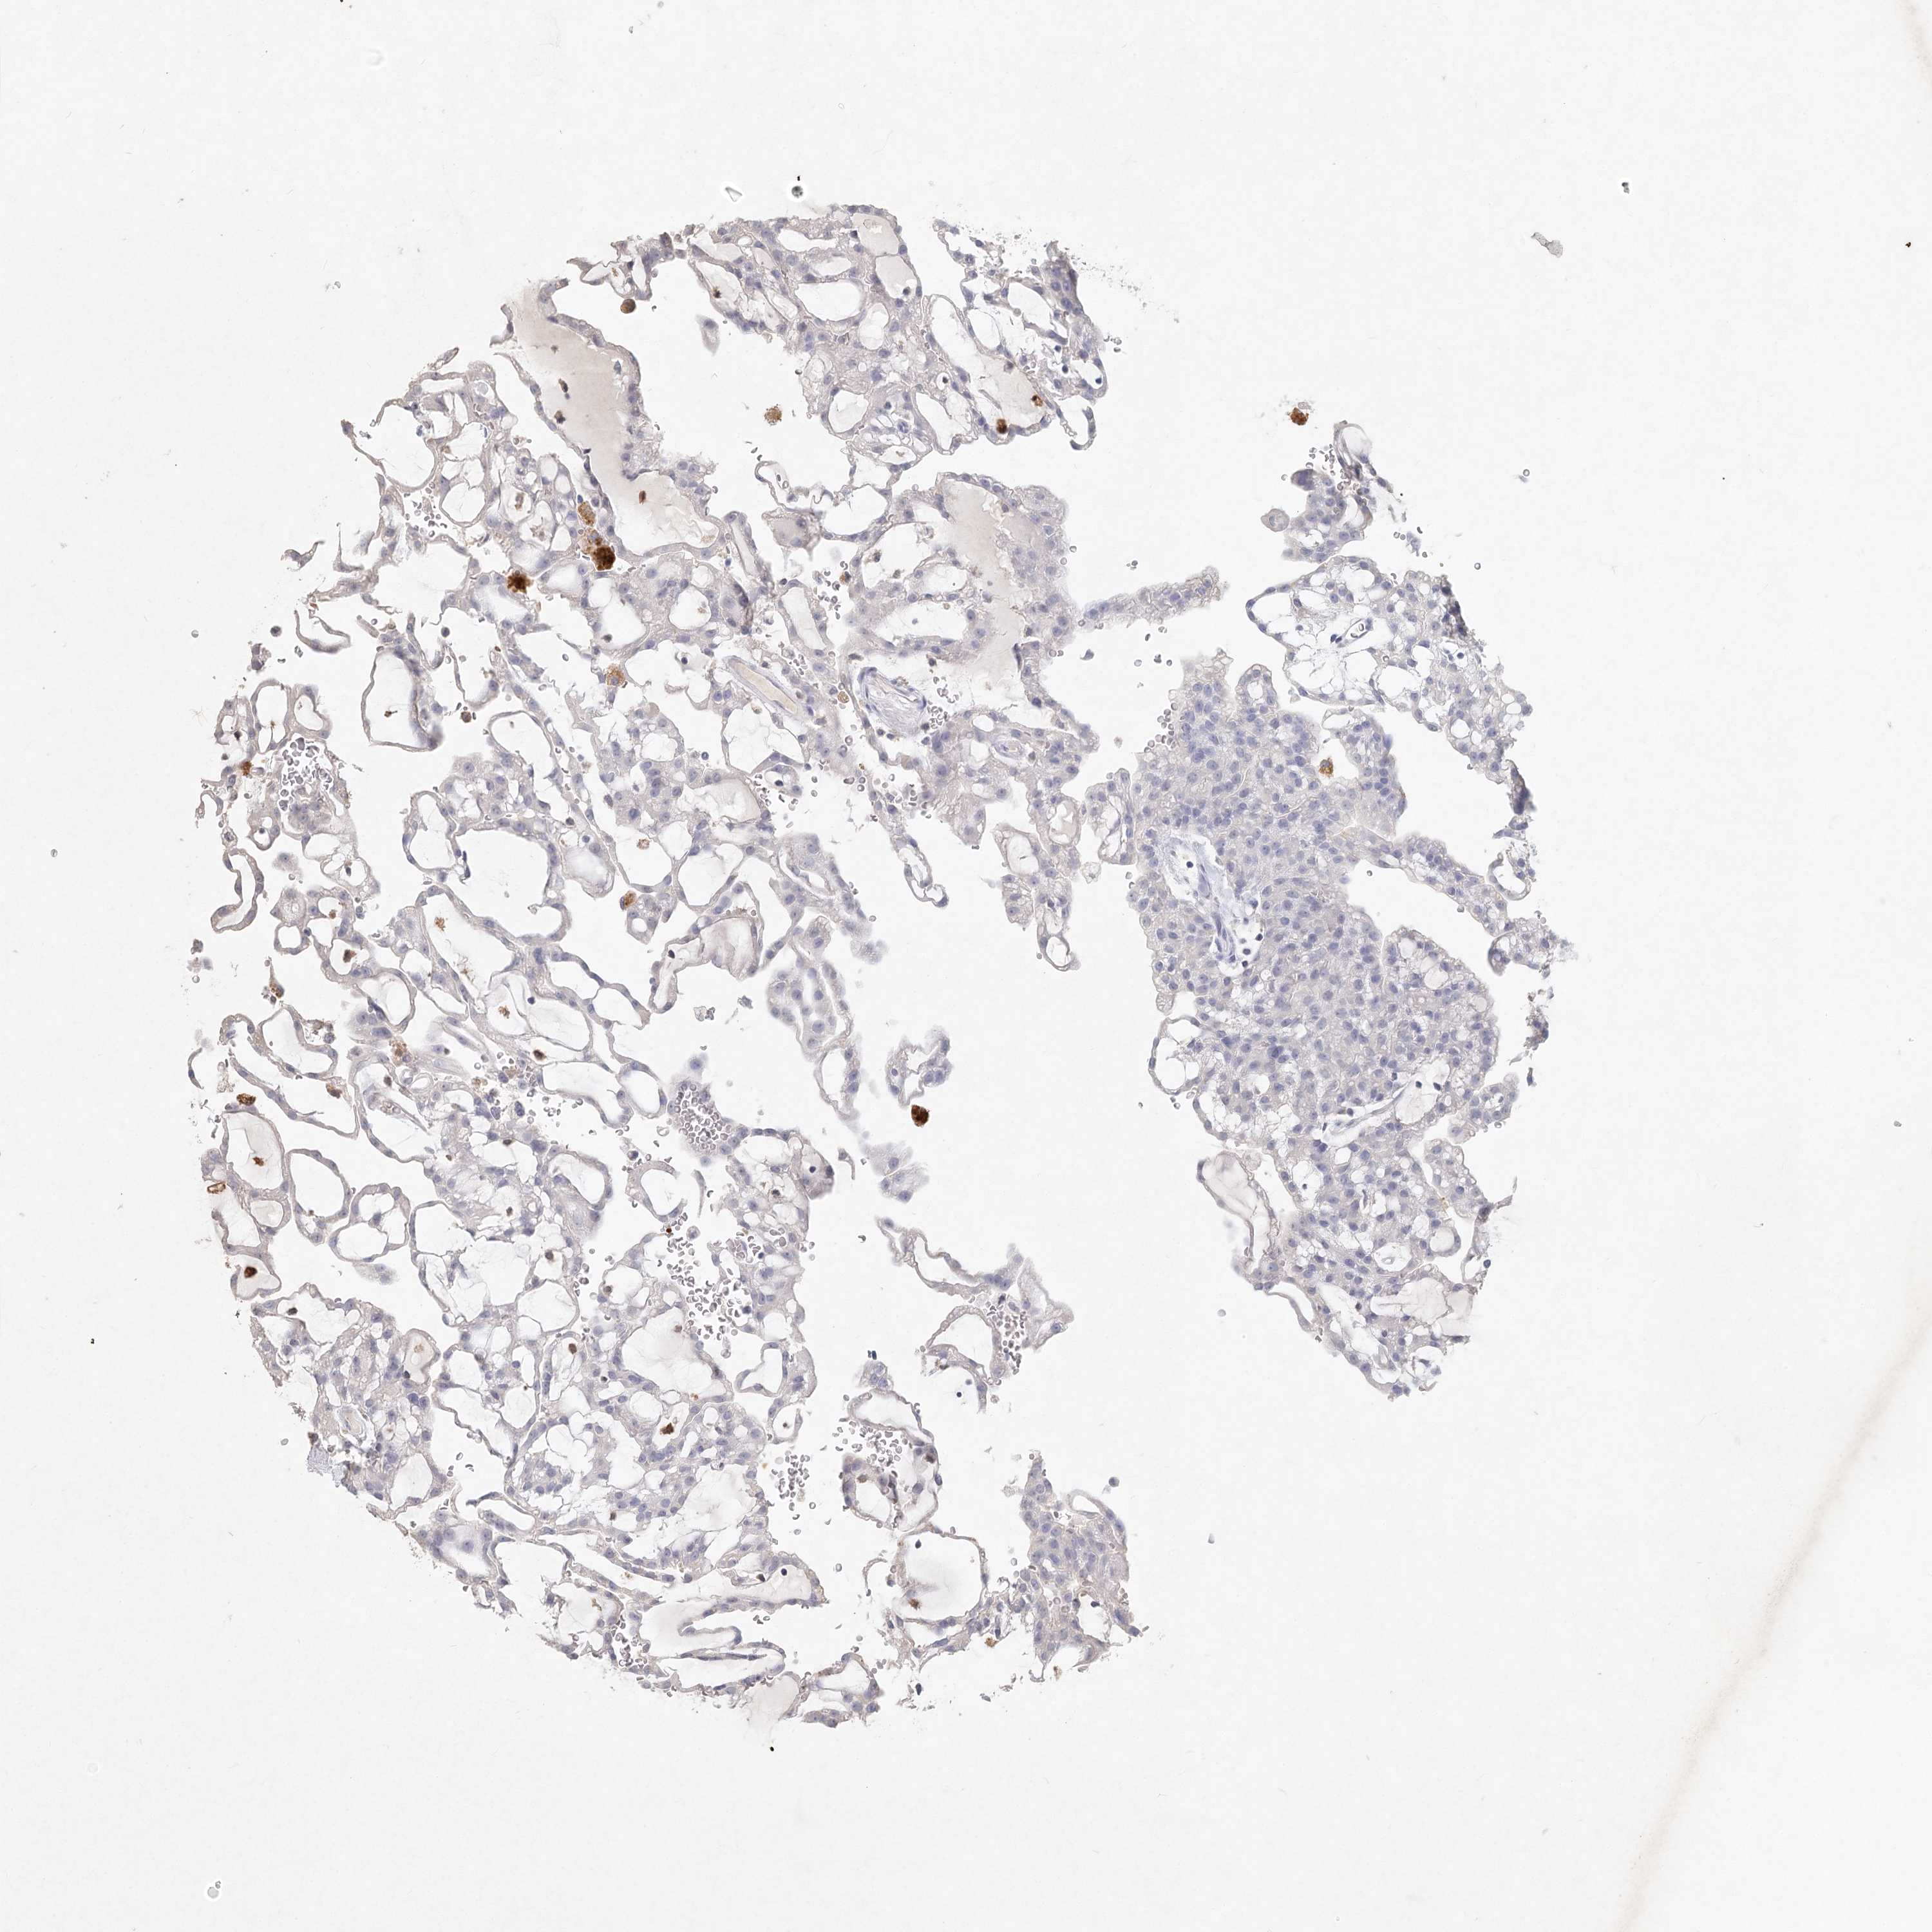

CANCER RENAL CANCER Show tissue menu

KICH TCGA KIRC TCGA KIRC VALIDATION KIRP TCGA PROTEIN RCC CPTAC PROTEIN EXPRESSION